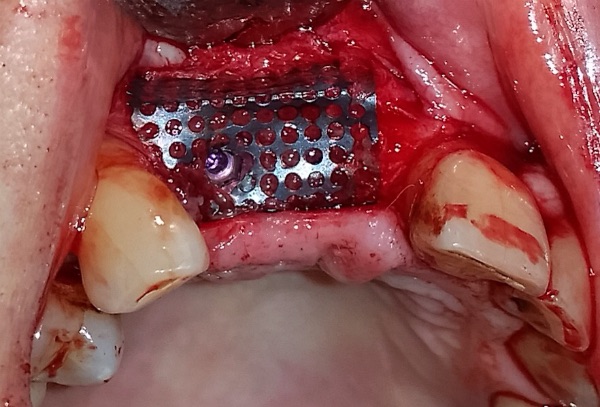

Intervento di chirurgia implantare ed innesto osseo con Mesh in Titanio contestuale eseguito con la tecnica del Guided Bone Rigeneration ( G.B.R. ) per ricreare i corretti volumi ossei in paziente con grave perdita ossea dovuta a Parodontopatia.